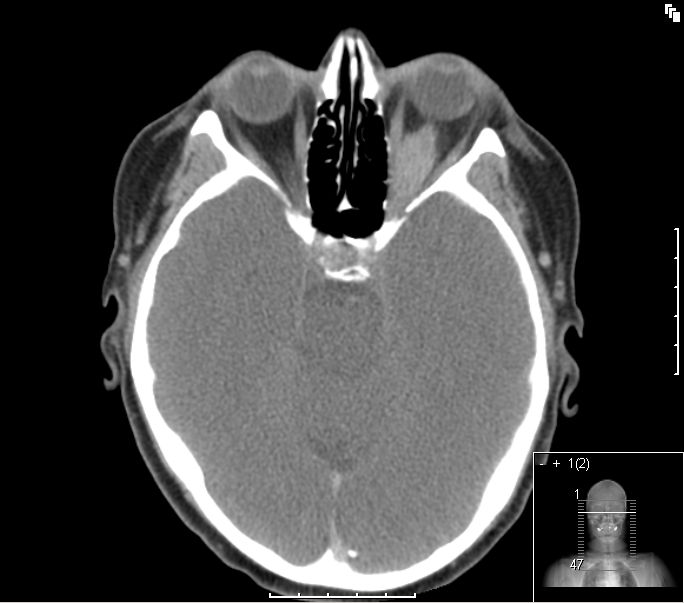

![]() Orbita |